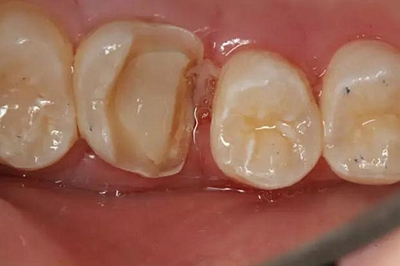

患者男性,35歲,B6銀汞充填后食物嵌塞,要求重新充填,口內(nèi)檢查見B6近中鄰頜面銀汞充填物,局部缺損,有繼發(fā)齲,去除原充填物及繼發(fā)齲,發(fā)現(xiàn)齲壞位于牙齦下方,給予冠延長(zhǎng)手術(shù),同期嵌體預(yù)備,后一次性取模。(同樣設(shè)計(jì)為齦上邊緣)

硅橡膠取模后,灌注模型,科爾琥珀樹脂制作嵌體。

一周后拆線,口內(nèi)試戴合適,粘結(jié)嵌體。